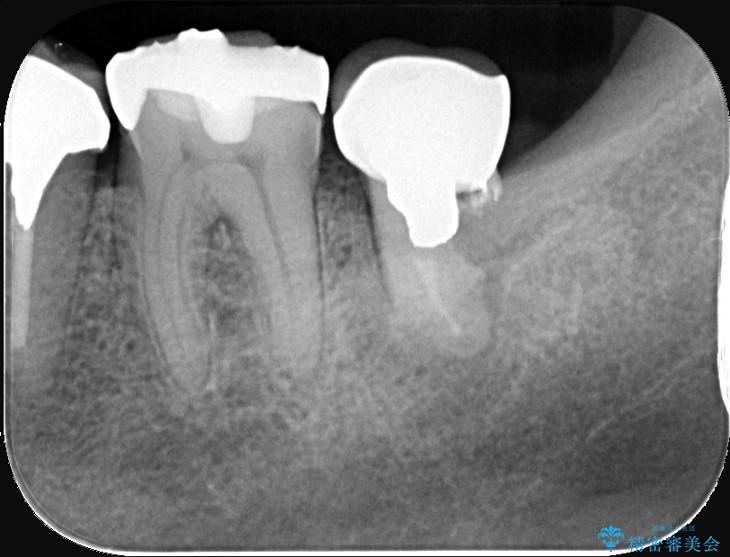

- 過去にヘミセクションが行われていたと思われる左下7番は、大きな歯根嚢胞および根尖病変が認められ、さらに骨縁下カリエスを伴っており、歯肉には瘻孔が形成されている状態でした。

保存は困難と判断し、左下7番は抜歯即時インプラントによる治療を行いました。

また、左下6番には形態が不自然で適合不良のセラミックインレーが装着されていたため、二次カリエスのリスクを考慮し、オールセラミッククラウンによる治療を行いました。